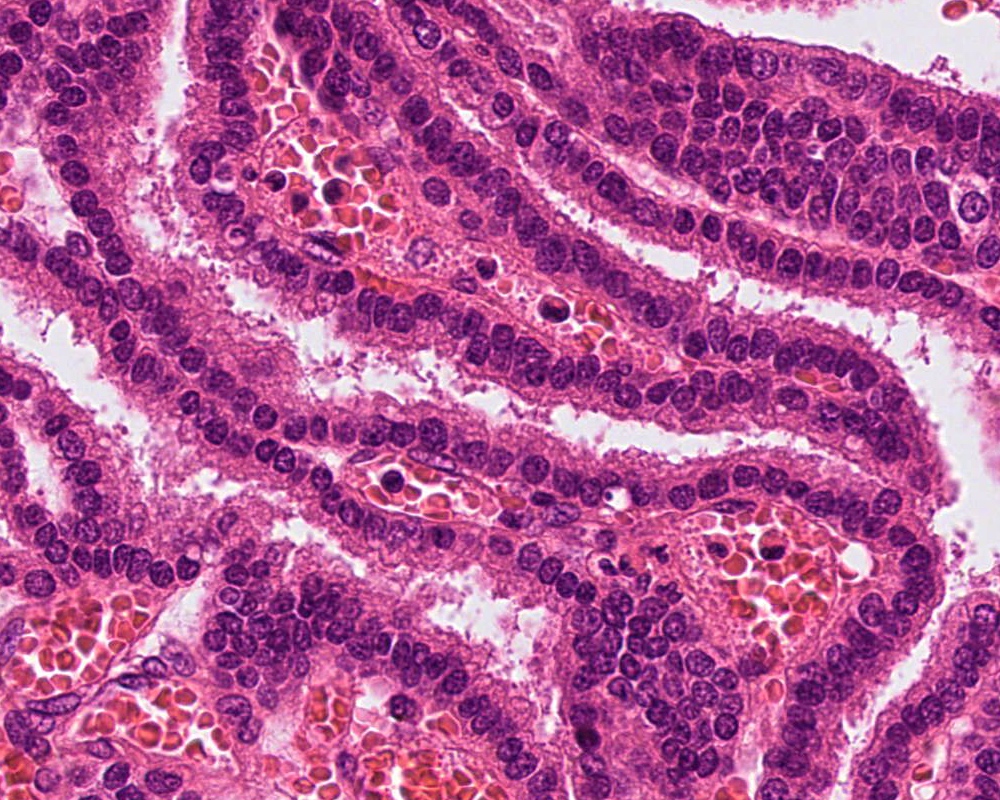

- Choroid plexus carcinoma (CPC, WHO grade 3):

- Frankly malignant

- High cellularity, hyperchromatic nuclei and nuclear pleomorphism

- Blurring of papillary pattern and solid arrangement

- Frequent mitoses (> 5/10 high power fields), necrosis, with or without brain invasion

Microscopic (histologic) images